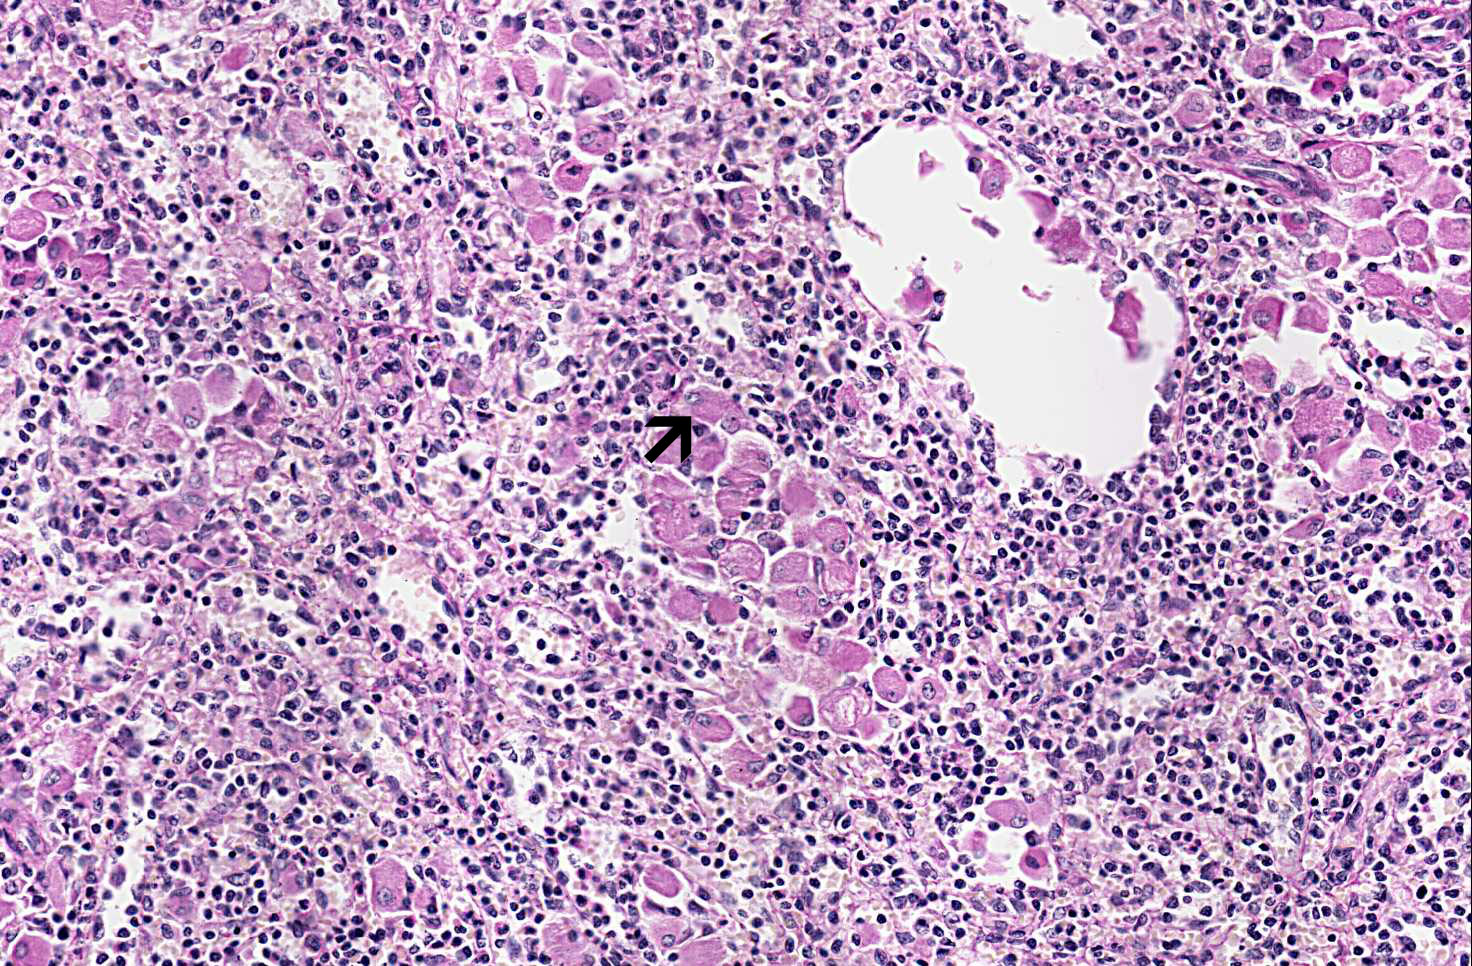

Area 1: The Gaucher cells are present through out the spleen and lead to splenomegaly. Note that many Gaucher cells have a vaguely laminated cytoplsm (arrow).

• On higher magnification, the spleens has clusters of large polygonal cells with a large, often centrally located nuclei (Area 2). The cytoplasm of these cells has a vague laminated pattern resembling crumbled tissue paper. These cells are known as Gaucher cells and they are highly suggestive of Gaucher's disease.